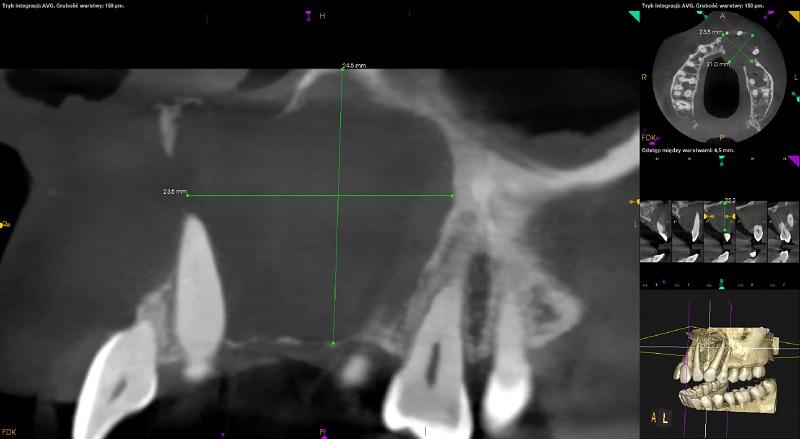

W okolicy 21-24 rozległe ognisko osteolityczne o charakterze torbieli (24,5mm x 23,5mm x 21mm). Zmiana powoduje dowargowe przemieszczenie zębów 21,22,23 (resorpcja korzeni zębów niewidoczna) oraz duże rozdęcie zarysu wyrostka po stronie przedsionkowej i podniebiennej. Obejmuje blaszkę zbitą po stronie przedsionkowej i podniebiennej oraz blaszkę kortykalna dna zatoki szczękowej. Przylega do kanału przysiecznego oraz ściany dolnej przewodu nosowego dolnego lewego z zachowaniem ciągłości. Obraz radiologiczny może odpowiadać rozległej torbieli lub rogowaciejąco-torbielowatemu guzowi zębopochodnemu (KCOT) -

do konsultacji chirurga szczękowo-twarzowego.

Podejrzenie fenestracji w okolicach wierzchołków korzeni policzkowych zębów 14 i 24. Korzeń podniebienny zęba 24 objęty zmianą.